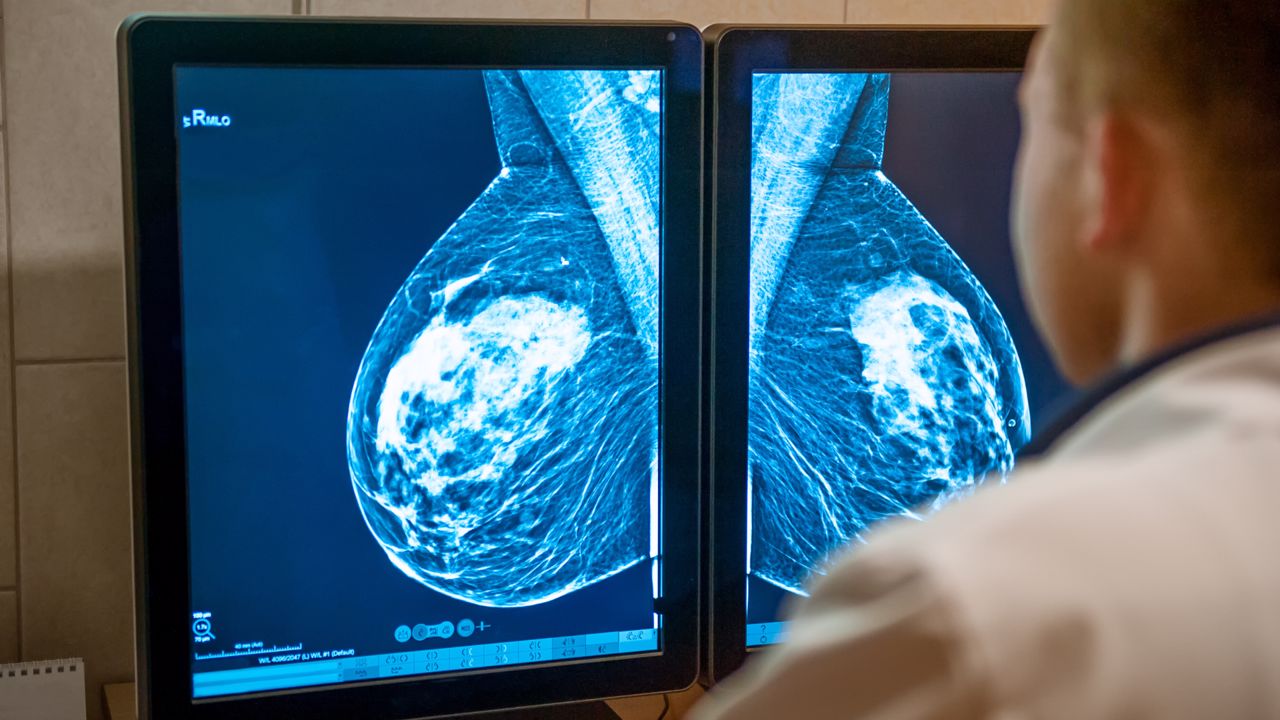

Hay que recordar que la autoexploración no puede ni debe sustituir en modo alguno a las pruebas y exámenes regulares, como la mamografía, que puede detectar bultos u otras microcalcificaciones con extrema precisión.

El método más eficaz en la actualidad para la detección precoz del cáncer de mama es la mamografía. La ecografía también puede ser un examen muy útil, sobre todo para las mujeres que aún son jóvenes.